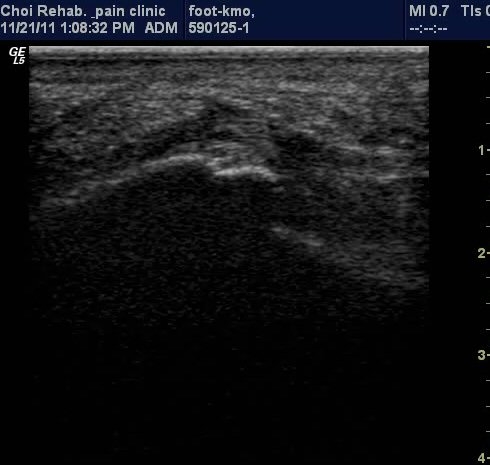

ÃÊÀ½ÆÄ ¼Ò°ß

µÚ²ÞÄ¡ Á¾´Ü¸é°Ë»ç¿¡¼­ Á·Àú±Ù¸·ÀÇ Àú¿¡ÄÚ ºÎÁ¾ÀÌ ¶Ñ·ÈÇÔ(±×¸² 1, 2).

Ⱦ´Ü¸é°Ë»ç¿¡¼­µµ Á·Àú±Ù¸·ÀÇ Àú¿¡ÄÚ ºÎÁ¾ÀÌ ¶Ñ·ÈÇÔ(±×¸² 3).